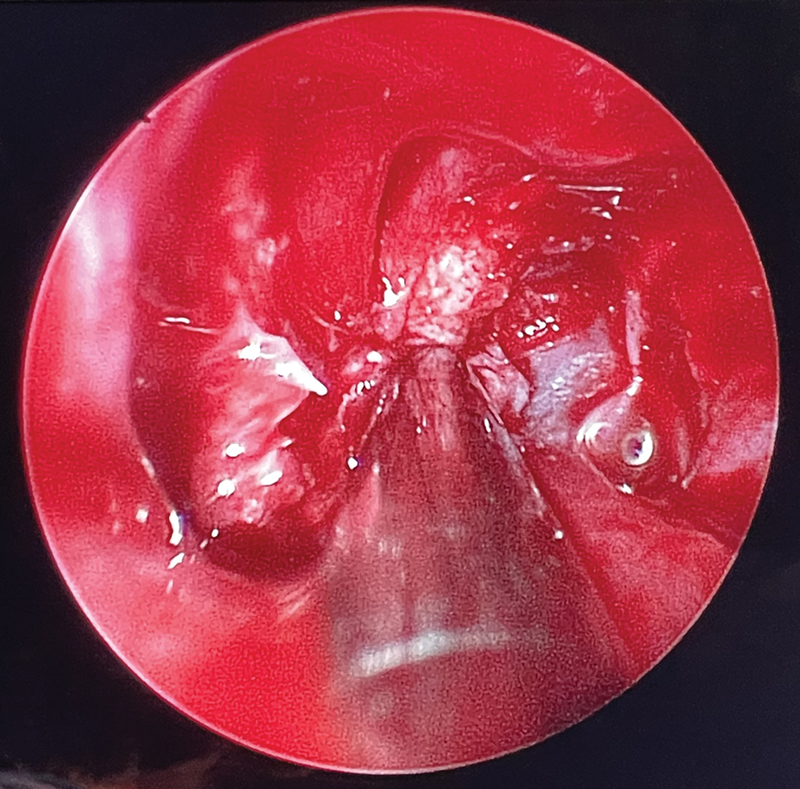

Case description: A 7-month-old male with a family history of osteopetrosis presented with hepatosplenomegaly. The infant was diagnosed with osteopetrosis based on radiological findings and genetic testing. Ophthalmologic examination and magnetic resonance imaging showed evidence of bilateral optic nerve compression. Endoscopic transcaruncular optic nerve decompression was not attainable The patient underwent a bilateral expanded endoscopic endonasal medial orbital wall and optic canal decompression.

Conclusion: This is one of the few reported cases of endoscopic endonasal optic nerve decompression surgery on an infant. Endoscopic endonasal optic nerve decompression surgery is a viable and effective treatment option for optic nerve compression in infants with osteopetrosis, especially in cases where cost of surgery is a limiting factor for patients. This approach provides direct access to the optic canal with minimal morbidity, offering significant potential for visual recovery, and an improved quality of life. Our patient represents the youngest reported infant in the literature, demonstrating the potential for undergoing this surgical approach at the earliest possible age to aid with his prognosis.